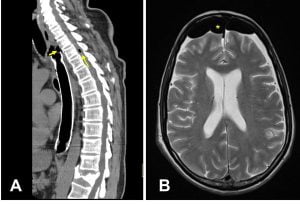

Fístula esófago intra-raquidiana complicada de meningite, verificando-se (A) descontinuidade da prótese esofágica e componentes gasosos no espaço intra-raquidiano (seta) e (B) intracraniano (*).